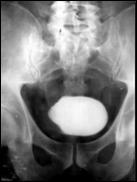

4.1. Radiografia renovezicala simpla si UIV raman examenele de baza pentru diagnosticul etiologic al oricarui pacient cu hematurie. Tumorile vezicale au drept semn radiologic cardinal imaginea lacunara pe cistograma urografica. Tumorile infiltrative pot induce modificari ale supletii peretelui vezical, care devine rigid, inextensibil, retractat etc. in zonele patologice. Ureterohidronefroza sau rinichiul mut sunt rezultatele invaziei si obstructiei ureterelor intramurale induse de tumorile solide, infiltrative (Fig.27,28,29).

Figura 28. Imagine

lacunara de 2,8/2 cm, in aria vezicii urinare, sugerand tumora

vezicala.

a. b.

Figura 31. a,b. Tumora

vezicala situata in trigon. Figura 32. Tumora vezicala infiltrativa

situata in hemivezica stanga